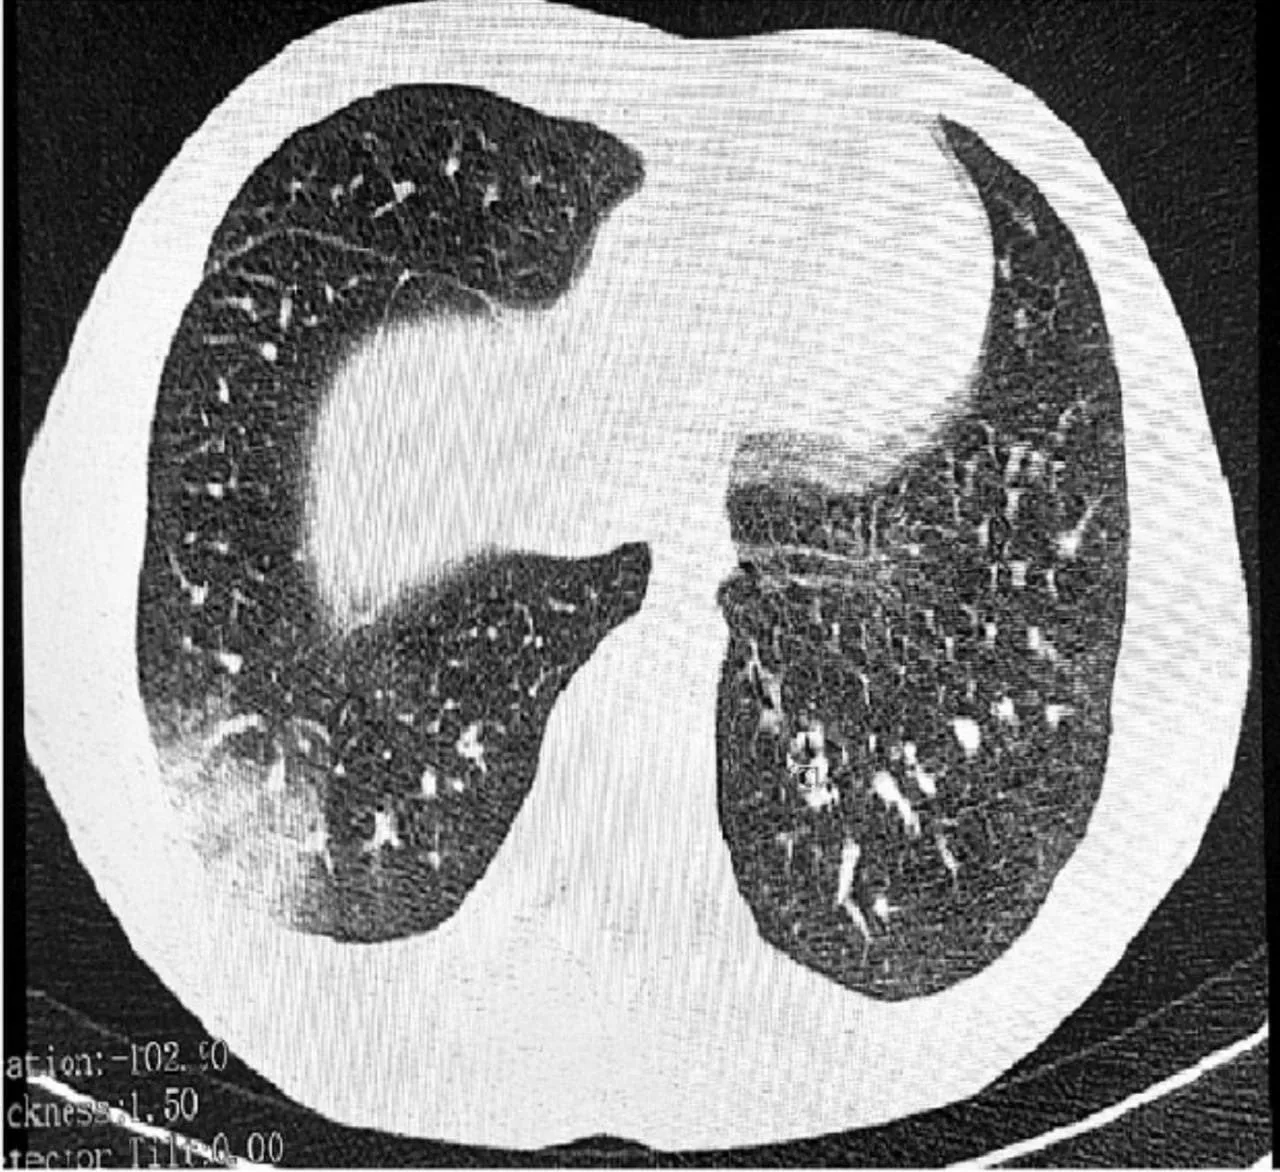

Такой ужасный диагноз получили подростки из Томска, которые фанатели от вейпа и одноразовых сигарет. «Попкорновой» болезнь называют, так как при прослушивании легких они издают треск, как при готовке попкорна.

Пока медицина не научилась бороться с этой болезнью.